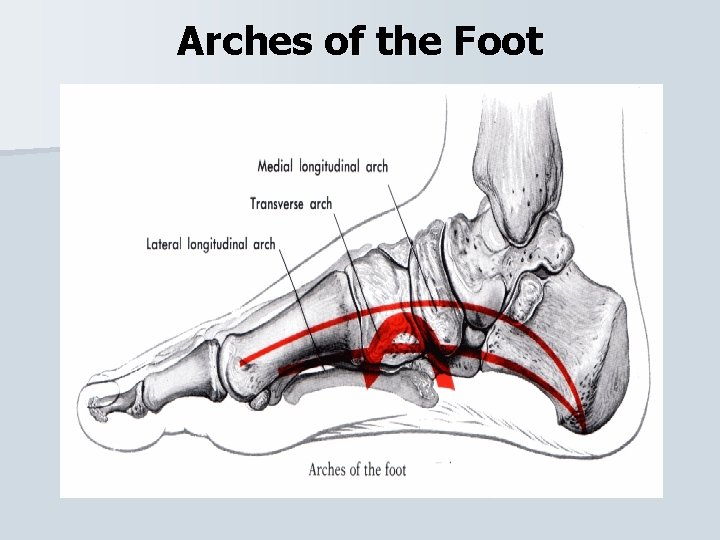

Arches of the Foot